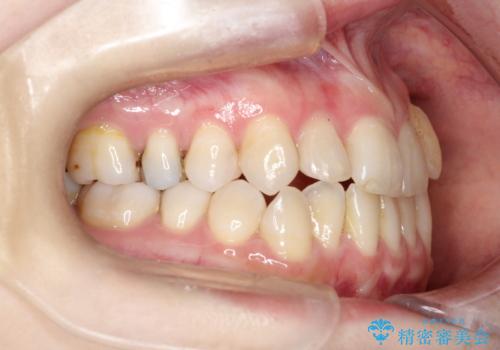

- 左上の八重歯の改善を希望され来院された患者様です。

初診時の歯並びの状態としては、上下ともに前歯部中心としたの中等度のがたつき(叢生)があり、全特に左上の前歯は1本だけ引っ込んでおり、犬歯は外に飛び出した状態でした。

抜歯は行わず上顎の奥のスペースを利用して歯をスライドする方法の他に歯列弓の拡大やディスキング(歯と歯の間の隙間を作る処置)を行い叢生を改善しましています。

歯の大きさの不揃いが原因の正中のズレは、ディスキング量を調整することで合わせました。

矯正装置としてはマウスピースを使用しています。